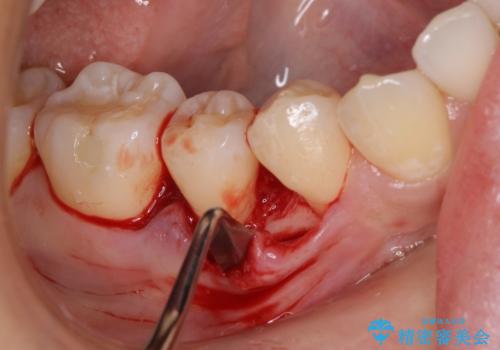

患者様は、他院で右下の歯を抜歯かもと言われました。全体の歯周病はなく、右下の1歯だけ骨が極端に減少していました(初診時歯周ポケット7mm。通常は3mm以下。)。その歯だけ咬合が強いことが原因と考えられたため、咬合を弱くする処置と減少した骨を再生する処置が必要になりました。

骨の再生治療手術をして10か月経過観察をしたのち、骨を平坦化する手術を行い、治療終了となりました。